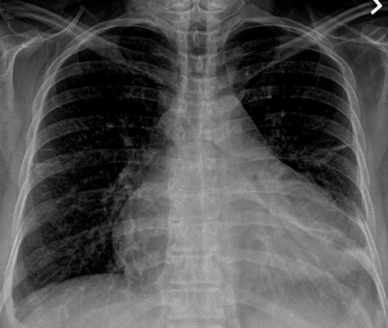

CXR of pericardial effusion: Above are images of pericardial effusion on chest X-ray. On the left, cardiomegaly with a slight water bottle appearance can be appreciated. In addition, a retrocardiac air-fluid level with the air lower than the fluid despite the upright position of the patient is indicative of a pericardial effusion. The fluid is contained within the pericardium and sitting atop some aerated lung, creating this reverse air-fluid level. On the right, the later film shows the “Oreo Cookie Sign” of a vertical opaque line between 2 radiolucent vertical lines indicative of pericardial fluid between the pericardial and epicardial fat. With large pericardial effusions, widening of the subcarinal angle may also be seen.